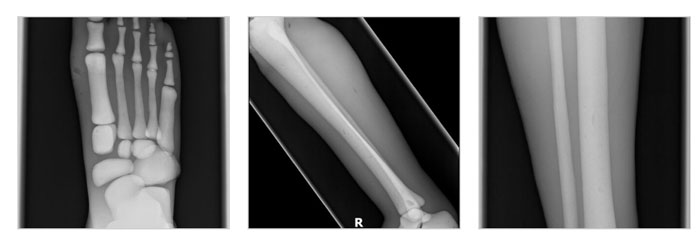

LG-A02成人腿部模體,LG-A02男性腿部模型,用于 X 射線 CT 和超聲波的成人腿部(肌肉)模型是一種基于人類男性腿部平均解剖結(jié)構(gòu)設(shè)計(jì)的逼真模型。它具有所有基本的骨骼和軟組織特征,使其成為學(xué)習(xí)、研究和測(cè)試醫(yī)學(xué)成像設(shè)備的理想工具。

LG-A02 可用于研究不同方向和定位技術(shù)的多種診斷性 X 射線 CT 和超聲程序。根據(jù)要求,該產(chǎn)品可以根據(jù)不同的病理進(jìn)行定制,也可以用于特定的培訓(xùn)應(yīng)用。

LG-A02成人腿部模體,LG-A02男性腿部模型實(shí)物圖

LG-A02成人腿部模體,LG-A02男性腿部模型成像效果:

LG-A02成人腿部模體,LG-A02男性腿部模型成像效果